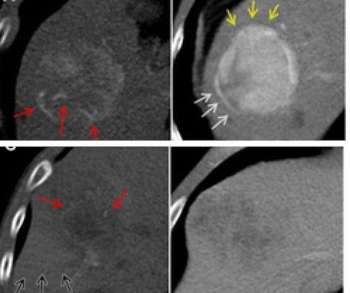

A hybrid computed tomography radiomics model demonstrated up to an 86 percent area under the curve in predicting microvascular invasion in patients with hepatocellular carcinoma in a recently published study.